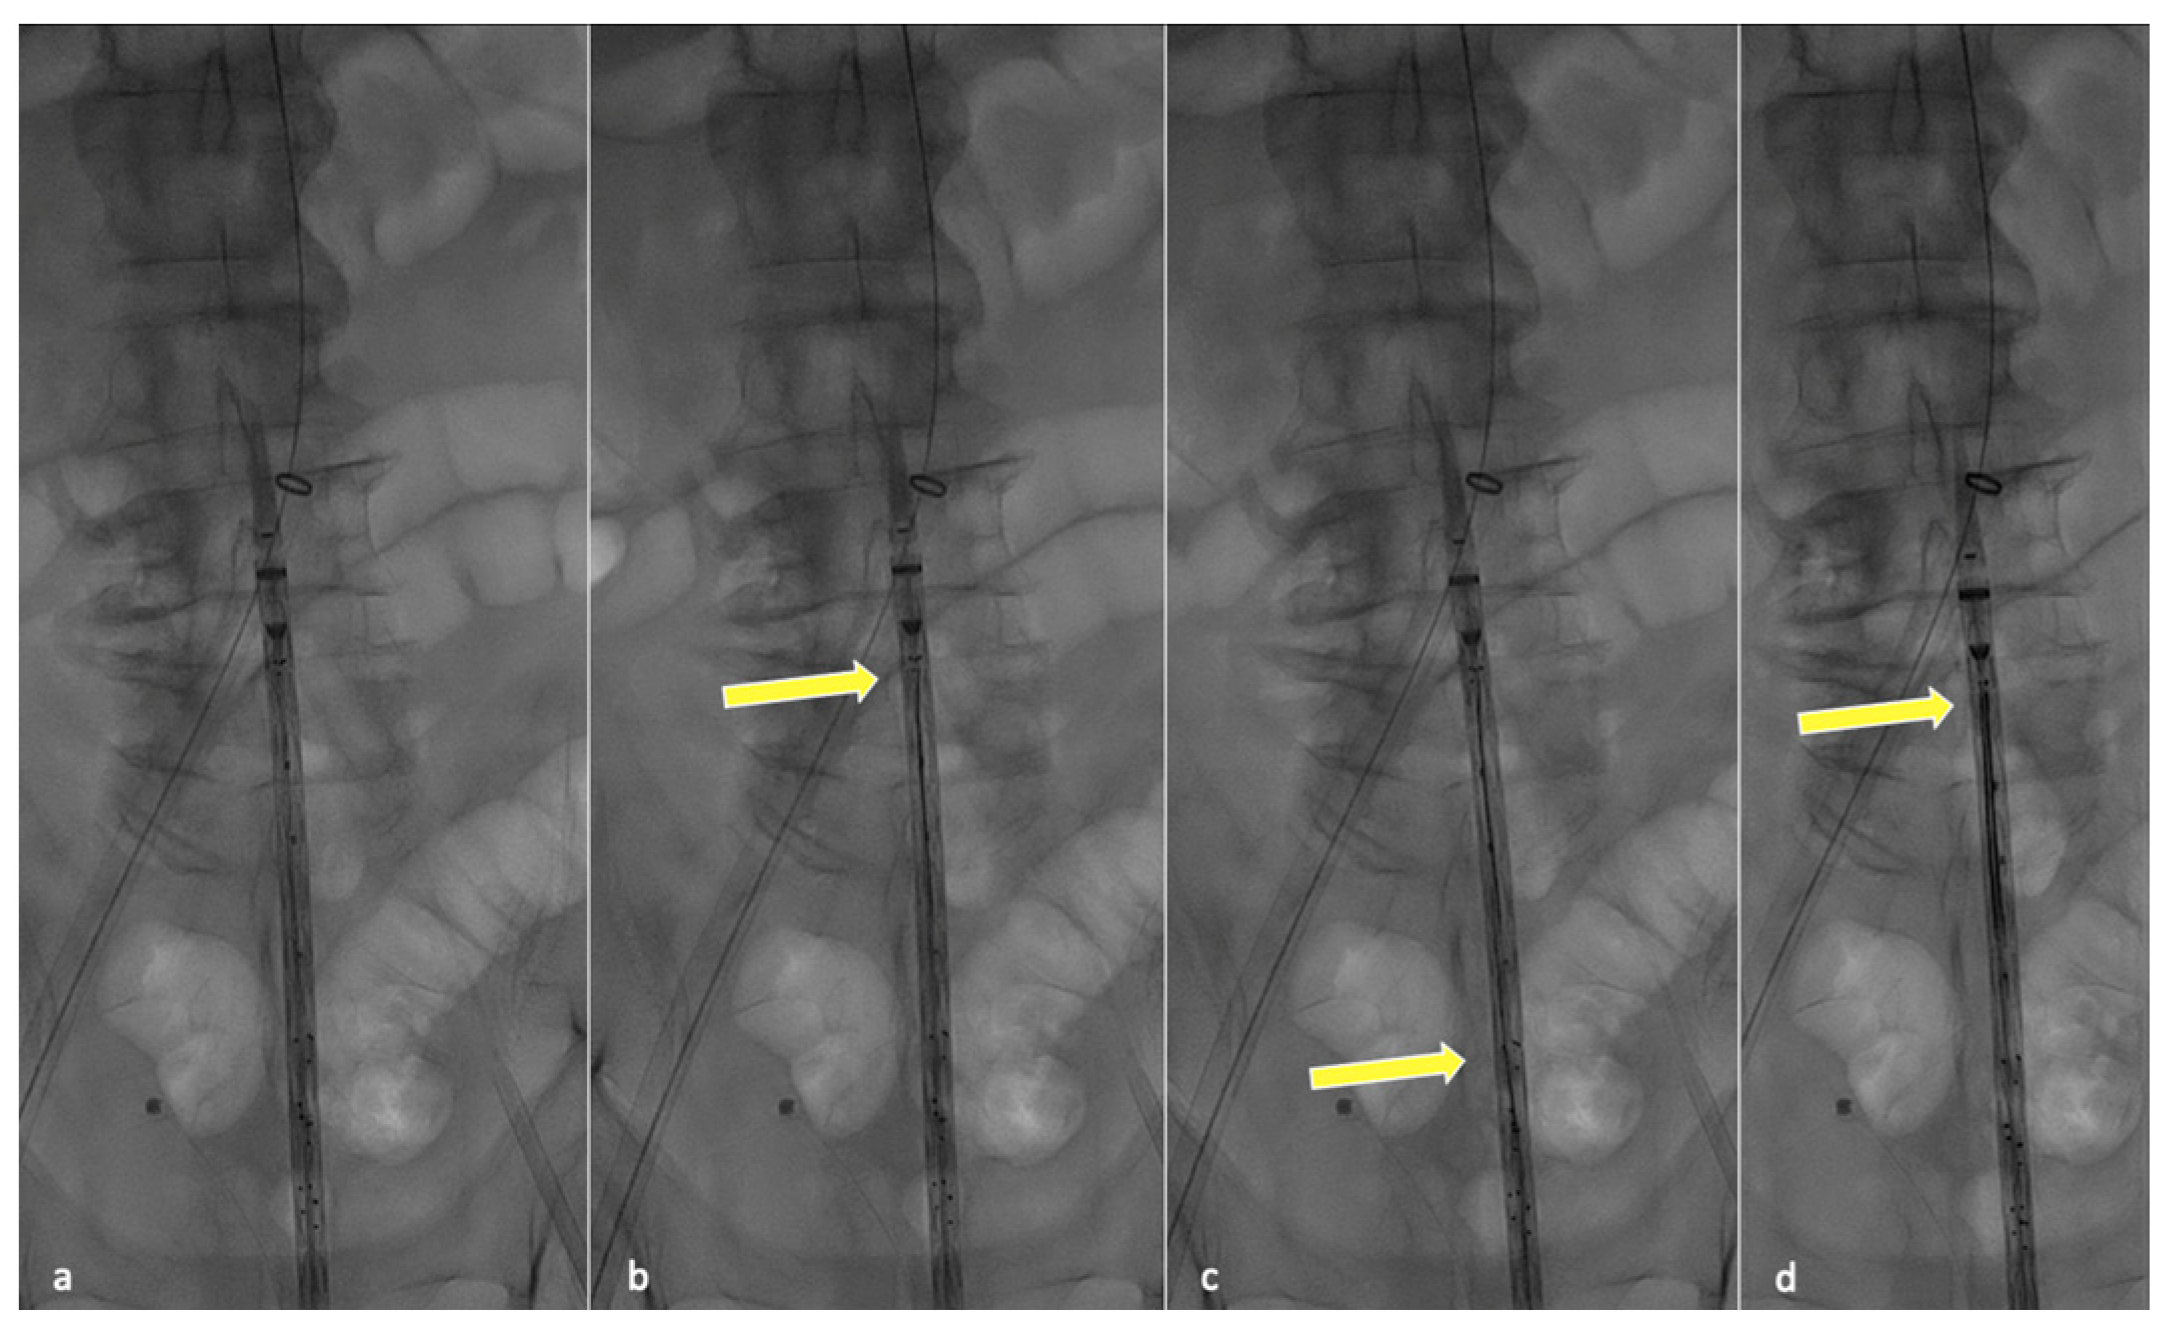

In order to perform partial endograft deployment, the device should be prepared before insertion by advancing, under fluoroscopy, all four dedicated 400 cm long 0.018″ non-hydrophilic guidewires through the corresponding microcatheters until their proximal end reaches the cranial graft’s edge (Figure 1).

Figure 1. Fluoroscopic check during guidewire anticipated advancement. Graft leaning on patient body (a), yellow arrow pointing at the tip of the first positioned guidewire (b), second guidewire advancement (c) and final results after all guidewires have been correctly advanced (d).